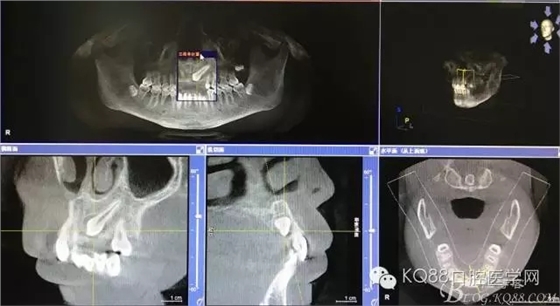

图1.术前的cbct影像检查:23位于腭侧、牙齿位置比较高。